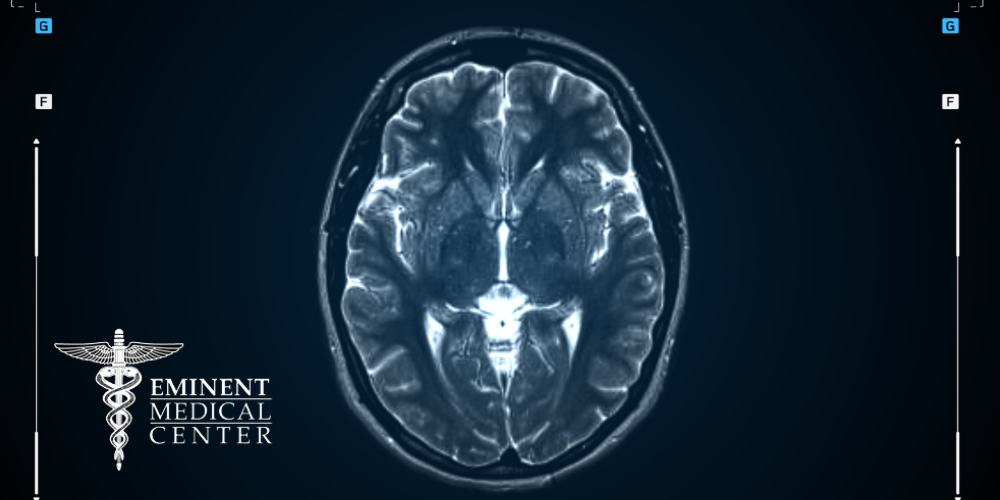

MRI

In diagnosing trigeminal neuralgia, while a physical exam and patient history often provide critical insights, advanced imaging techniques such as magnetic resonance imaging (MRI) play a significant role, particularly in cases where the determination is not straightforward. Most patients with trigeminal neuralgia undergo MRI scans to detect any structural abnormalities or underlying causes contributing to their symptoms. These scans help doctors rule out other conditions that may mimic trigeminal neuralgia, such as tumors or vascular compression of the trigeminal nerve.

By examining the brain and surrounding structures in detail, MRI scans assist in accurately diagnosing the condition and assessing the seriousness of nerve compression or any other potential contributing factors. With MRI’s ability to provide detailed images of the head and neural structures, doctors can better understand the frequency, advancement, and seriousness of trigeminal neuralgia, thereby guiding appropriate treatment strategies tailored to each patient’s specific needs.